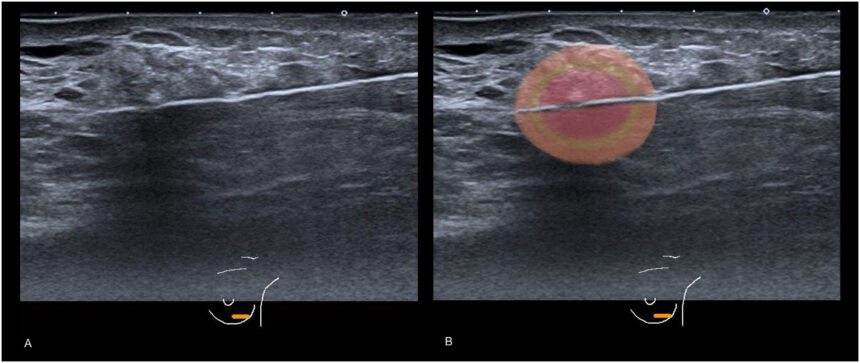

Las lesiones cerebrales de regiones subcorticales se realizan por lo general haciendo pasar una corriente eléctrica a través de un electrodo. Se guía éste de modo que su extremo llegue al lugar adecuado. El paso de la corriente a través del tejido cerebral produce una alta temperatura que destruye las células cercanas a la región que rodea la punta del electrodo. Las lesiones producidas con este método destruyen todo lo que se encuentra en las cercanías de la punta del electrodo; somas neuronales y axones de neuronas que atraviesan la región.

Un método más selectivo es emplear un aminoácido excitador como el ácido caínico que destruye las neuronas estimulándolas hasta destruirlas. A este tipo de lesiones se les llama lesiones excitotóxicas. Cuando se inyecta a través de una cánula un Aa excitador destruye los somas celulares vecinos, pero no los axones de las diferentes neuronas que pasan por alrededor.

Cuando se producen lesiones subcorticales siempre se causan daños adicionales en el encéfalo.

Inevitablemente se produce un cierto grado de lesión incluso antes de activar el dispositivo de lesión o de iniciar la infusión. No podemos limitarnos a comparar la conducta de los animales lesionados con la de animales de referencia intactos, puede que la causa de alguna de las alteraciones comportamentales sea el daño fortuito de las regiones cerebrales por encima de la lesión. Lo que se hace es una lesión falsa: se hace lo mismo que se haría para producir la lesión, excepto activar el dispositivo de lesión o iniciar la infusión. Este grupo de animales sirve de grupo control: si la conducta de los animales con lesión es diferente de la de los animales control se puede concluir que las lesiones son la causa de las alteraciones comportamentales.